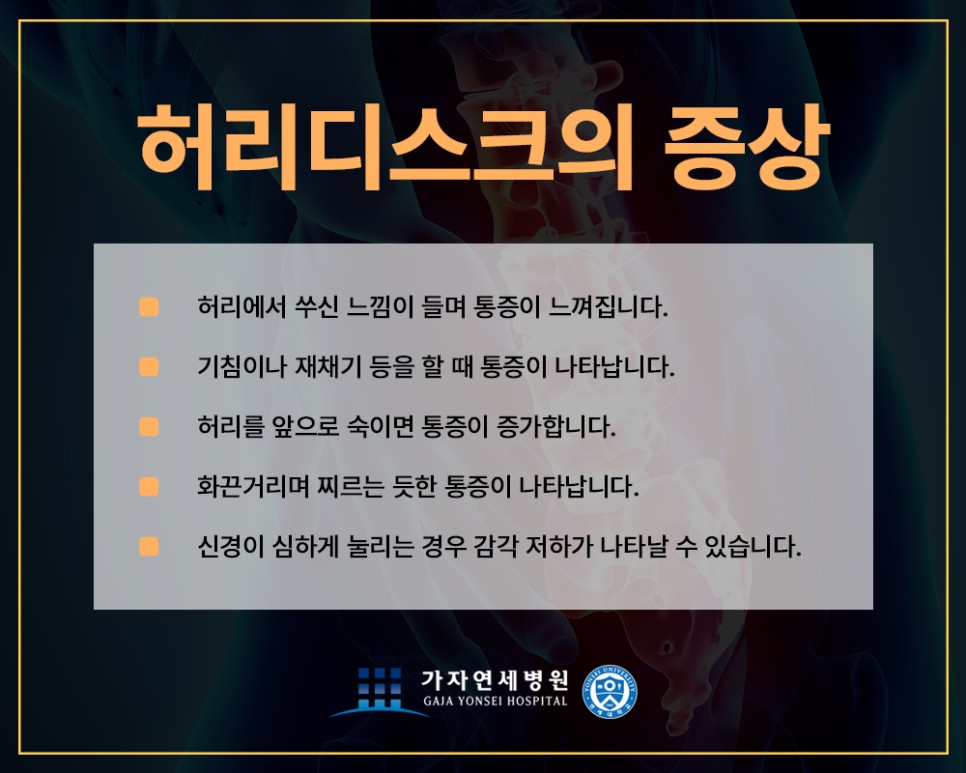

허리디스크 증상

- 허리의 묵직한 통증과 쑤시는 느낌이 지속적으로 느껴진다.

- 누워서 다리를 들어 올릴 때 통증이 느껴진다.

- 기침이나 재채기를 할 때 허리에 통증이 있다.

- 허리를 움직이거나 장시간 같은 자세를 유지하면 통증이 발생한다.

- 장시간 앉아있거나 걸으면 다리가 저리고 당기는 통증이 있다.

이와 같은 증상이 나타난다면 허리디스크를 의심해 보시고 허리디스크 김포가자연세병원을 내원하여 정확히 검진을 받는 것이 좋아요.